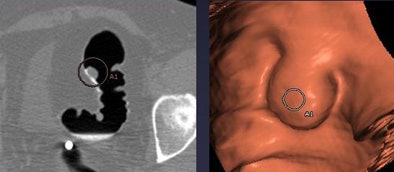

![]() |

| CAD missed a pedunculated polyp that was submerged in fluid in prone view (above) but detected it in both 2D and 3D when the fluid was cleared in supine view. |